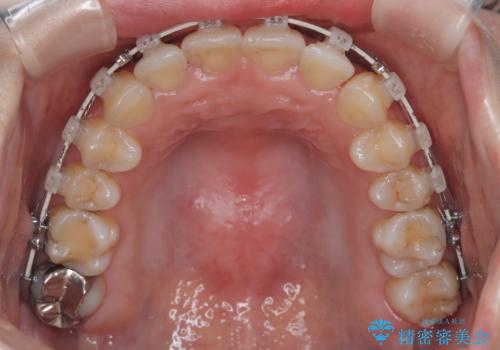

- 前歯の翼状捻転の改善を希望してこられた患者様です。

下顎の叢生はインビザラインで解決することがきましたが、上顎の捻転が完全には改善できなかったため、上顎は途中からワイヤーを用いて治療を行っています。

捻転の改善はインビザラインで苦手とするところですので、うまく治らない場合はワイヤーを提案しています。